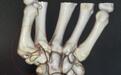

手术前刘女士手部影像图

在该院骨科门诊,医生接诊后详细询问刘女士病史,并为其进行了相关检查。发现刘女士左手第一腕掌关节间隙几乎完全消失,形成大量骨赘,诊断为第一腕掌骨关节炎。

“第一腕掌关节炎是指拇指根部的关节由于劳损和退变而发生关节炎。”该院骨科手足外科负责人吴波介绍,第一腕掌关节是手最灵活的关节,拇指功能占手部功能的40%,主要就是依赖于第一腕掌关节活动。因此第一腕掌关节也最容易发生退变、损伤,且一旦发生病变,将严重影响手部的功能。